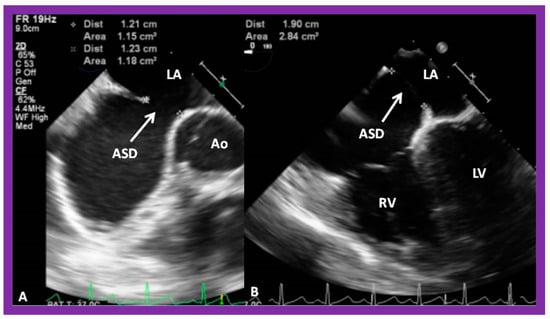

2. Diagnosis

4. Patient Selection for Device Occlusion